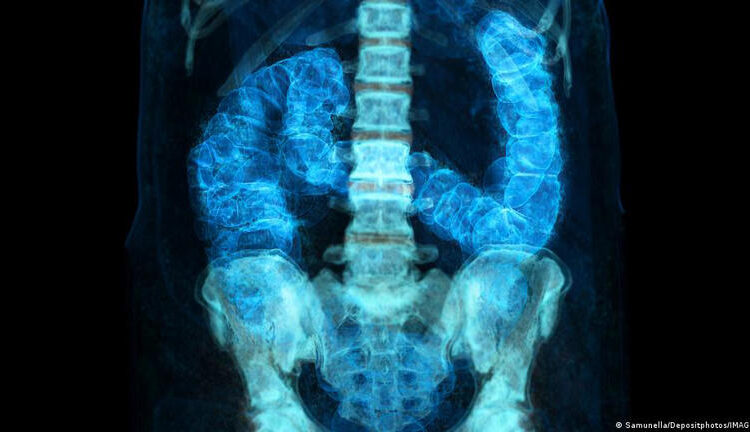

Además, dónde ocurre el cáncer a lo largo del colon en forma de signo de interrogación –comienza en un lado del abdomen y se curva hacia el otro antes de terminar con el recto– influye en qué tan agresivo es y cómo se trata. Marshall dijo que hay una marcada diferencia en dónde tienden a aparecer los tumores de las personas más jóvenes y mayores, otra pista que se está explorando.